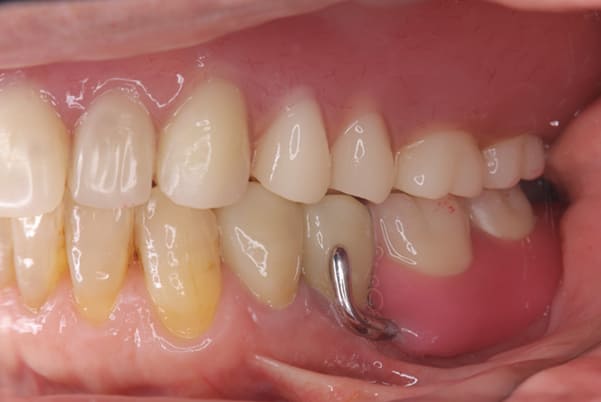

症例レポート[CASE.03]

入れ歯がガタつく、

見た目も改善したい

- 性別・年齢

- 女性(50代)

- 主訴

- 入れ歯がガタつく、何度調整してもよくならない。できれば見た目も良くしたい。

- 治療

- 上顎精密金属床部分入れ歯

- ジルコニアクラウン3歯

- 治療期間

- 約4か月間

- 費用

- 上顎精密金属床部分入れ歯:55万円

(ミリング、ラベット加工込み) - ジルコニアクラウン:11万円×3歯

合計:88万円(税込)

上あごに接する入れ歯に違和感がありになっていたとのことで、プラスチックが大きく削られた入れ歯をされていました。

そのため入れ歯の安定が悪く、お食事の際に入れ歯が動き、がたつきを感じられている状態でした。

前歯にバネにより見た目の問題も抱えておられました。

かみ合わせが低くなった歯を本来の高さに戻し、保険では使用できない歯に負担のかかりずらいバネで、歯の保存、審美性を確保しました。

前歯にバネを設定せず、見えない奥歯に維持力をもたせたバネを用い、またバネのかかる歯の負担軽減を目的に、被せ物は繋げることで強度を増す設計とすることで、入れ歯が動かずガタつき、審美性不良が解消されました。

部分入れ歯と対合歯

入れ歯を修理する中で、入れ歯の上あごの接触面積ではなく、厚みに対しての違和感と診断し、薄い金属を用いた従来の厚みを1/3程度にした入れ歯にすることにより違和感は消失しました。